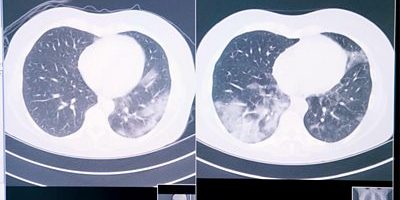

Пациенты с раком легких, проходящие курс иммунотерапевтического лечения могут возникать побочные эффекты, которые могут проявляться так же, как при Covid-19 и других заболеваниях легких.

Но сейчас Королевская больница Марсдена в Лондоне пробует использовать искусственный интеллект (ИИ), чтобы помочь определить, что вызывает симптомы.